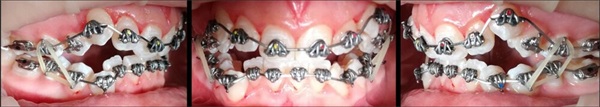

The Fastbraces Technology bracket systems have reduced orthodontic treatment durations to as little as 60–90 days. The case presented here (Figs. 1–5) is a 16-year-old female with a Class I occlusion on both sides, moderate crowding, and an open bite tendency. Interarch vertical elastics were used throughout the treatment.

Fig. 4: April 25

Fig. 5: May 16